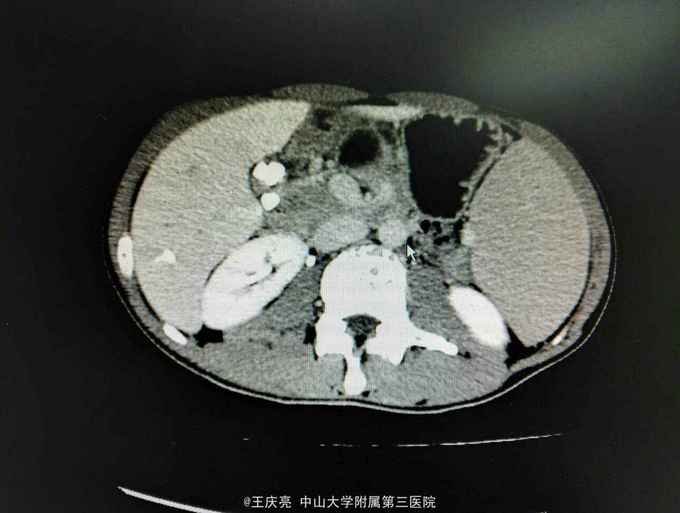

39岁男性,因胆源性胰腺炎治疗后一月就诊,1月前无诱因出现腹痛,于我院就诊,查AMY3890,CT示肝脾肿大,胆囊结石,胰腺炎,予积极治疗后好转出院,现拟行手术入院。既往有β地中海贫血病史,长期身目黄染,尿黄。

入院后查中度贫血,黄疸100,间胆为主,CT及彩超示结石,胆总管无结石,患者一般情况尚可,予行腹腔镜下胆囊切除术,术中见多发泥沙样结石,术后恢复可出院。因患者溶贫症状不重,血液科建议暂时不需要切除脾脏,患者也不同意积极切除。